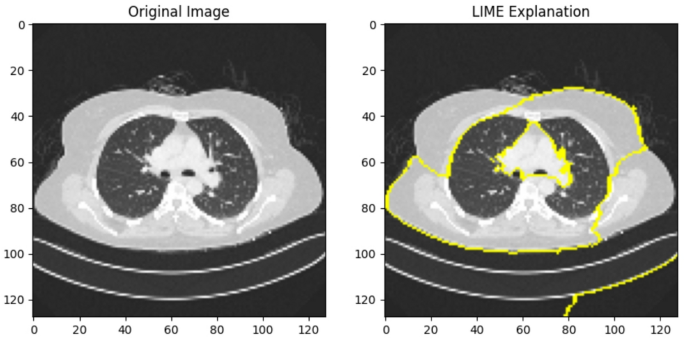

LIME-based interpretation of the global model’s lung cancer prediction.

Figure 14 illustrates the application of LIME on the global model after FL. The left panel shows the original lung CT scan image, while the right panel highlights the critical regions identified by the global model using LIME. These highlighted areas (marked in yellow) represent the region’s most influential in the AI’s decision-making process for predicting lung cancer. This explanation ensures model transparency and provides interpretable insights for clinicians, enabling them to understand and validate the prediction outcomes.